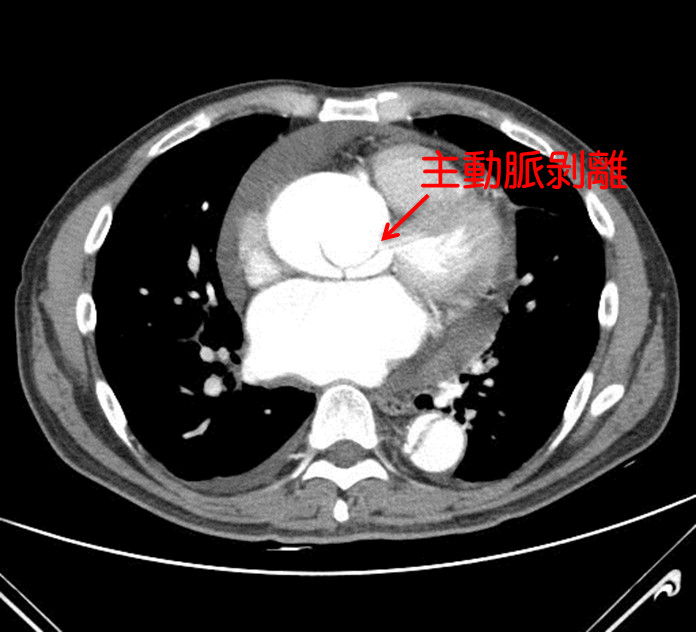

36歲藝人「小鬼」黃鴻升16日趴在家中臥室猝死,震驚全台,解剖後,檢方初判死因是主動脈剝離的心血管問題。急診室醫師說明,主動脈剝離會出現劇烈胸痛,「痛到背後,像被人從後砍一刀」;心臟外科醫師也說,猝死最常見的就是心肌梗塞,「有人連急救時間都沒有」,而主動脈剝離就像剝橘子皮,過程相當兇猛!

檢警18日會同法醫解剖,初步發現有主動脈剝離的狀況,疑似是心血管問題致死,詳細原因仍待法醫鑑定報告出爐釐清。據悉,小鬼2019年初曾被驗出三高,當時他下定決心3個月內靠運動、飲食降下來。

國泰醫院心血管中心部主任兼心臟血管外科主任侯紹敏也坦言,「主動脈剝離就像剝橘子皮」,主動脈市身體最大動脈,負責把心臟的血液通往全身,主動脈硬生生脫離,過程十分兇猛,患者會感覺胸口像被撕開一樣,通常有8成以上都會出現劇烈胸痛(前胸到後背)、呼吸困難、休克暈厥等,有高達50%的病患再發作當下就死亡。

誘發主動脈剝離的原因,侯紹敏指出,包含高血壓、高血脂等危險因子造成的動脈粥狀硬化,另也可能本身條件不佳,如先天主動脈狹窄及馬凡氏症候群等血管內壁組織比較脆弱。主動脈剝離發生有兩個高峰,其中一個較早在於40~55歲中壯年族群,主因在主動脈品質開始變差,一旦出現脆弱,承受不住血管壓力,很可能出現剝離,特別是做激烈運動、血壓又沒有控制好的情況,有可能突然發生。

急診室女醫師田知學也解釋過主動脈剝離,因主動脈壁有好幾層結締組織結合而成,如果層與層之間分開,讓血管裡面的血,流到新成立的腔室,這就是主動脈剝離,由於血管已經被剝開,管壁變薄,隨時都會破掉,急診室醫師聽到都會相當緊張。

有關主動脈剝離的症狀,田知學說,會出現劇烈胸痛,從前胸痛到後背,像是有人從背後砍了一刀,病人表現出來都像是受到極刑一樣疼痛,且剝離的情況可能會繼續往下延伸,所以不只是被人從背後砍一刀,可能繼續從上背砍到下背,再延伸到腳上。

▼主動脈剝離過程兇猛,心臟醫:有高達50%的病患再發作當下就死亡。(圖/資料照)